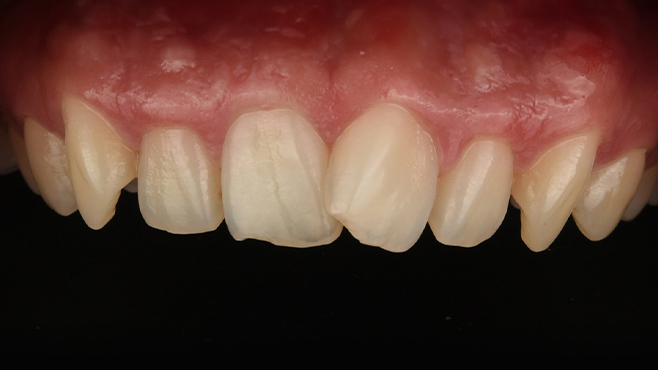

맞는 건 괜찮은데… 충치는 못 참겠습니다|20대 격투기 선수 치과 방문기